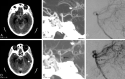

Results: Two hundred thirty patients (mean age, 54 years; 51% male) with CTA-negative SAH were identified. The pattern of SAH was diffuse (40%), perimesencephalic (31%), sulcal (31%), isolated IVH (6%), or identified by xanthochromia (7%). Initial DSA yield was 13%, including vasculitis/vasculopathy (7%), aneurysm (5%), arteriovenous malformation (0.5%), and dural arteriovenous fistula (0.5%). An additional 6 aneurysms/pseudoaneurysms (4%) were identified by follow-up DSA, and a single cavernous malformation (0.4%) was identified by MRI. No cause of hemorrhage was identified in any patient presenting with isolated intraventricular hemorrhage or xanthochromia. Diffuse SAH was due to aneurysm rupture (17%); perimesencephalic SAH was due to aneurysm rupture (3%) or vasculitis/vasculopathy (1.5%); and sulcal SAH was due to vasculitis/vasculopathy (32%), arteriovenous malformation (3%), or dural arteriovenous fistula (3%).

Conclusions: DSA identifies vascular pathology in 13% of patients with CTA-negative SAH. Aneurysms or pseudoaneurysms are identified in an additional 4% of patients by repeat DSA following an initially negative DSA. All patients with CT-negative SAH should be considered for DSA. The pattern of SAH may suggest the cause of hemorrhage, and aneurysms should specifically be sought with diffuse or perimesencephalic SAH.